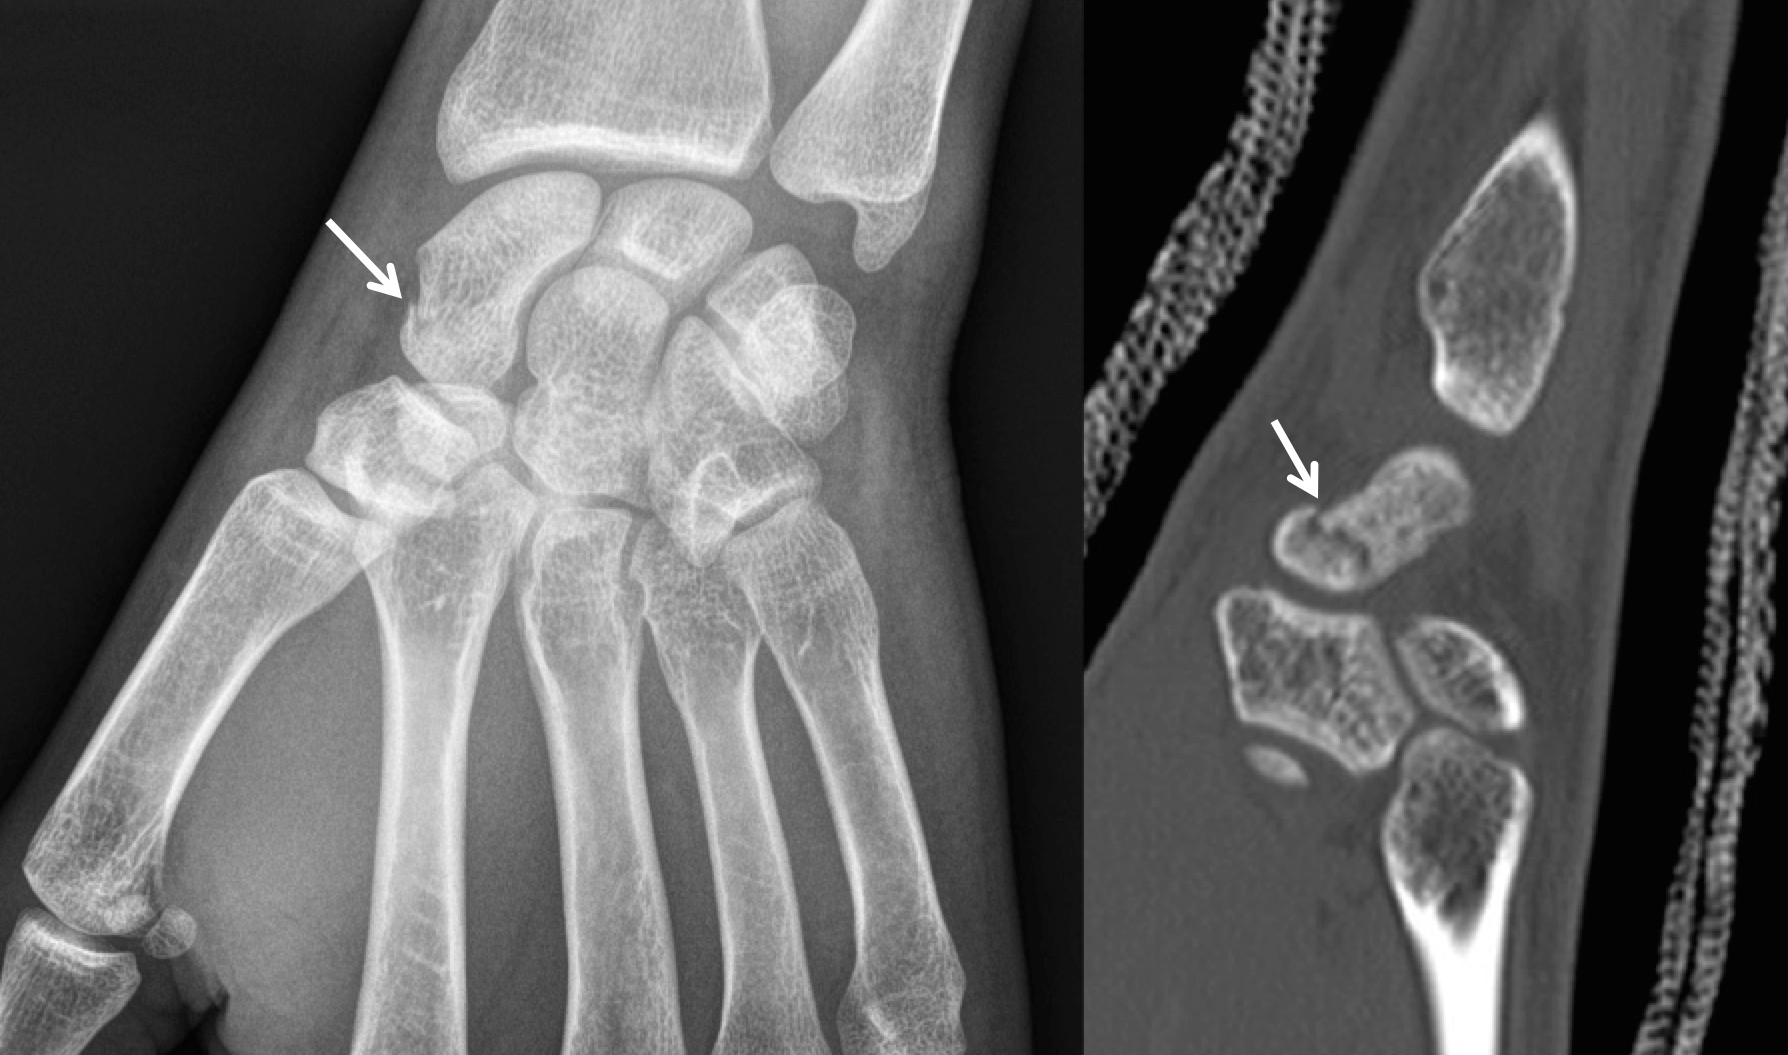

Symptômes. La fracture du scaphoïde entraine l'apparition d'un œdème douloureux au niveau du poignet. Cette fracture provoque des douleurs sur le bord externe et au niveau de la face dorsale du poignet. En général, le patient n'est pas en mesure de mouvoir son poignet correctement.. Il est un des plus grands des os du carpe (poignet) et a pour particularité d'avoir une grande mobilité et d'être très vulnérable lors des traumatismes du poignet ; le scaphoïde est l'os du carpe le plus souvent fracturé. Le mécanisme de fracture du scaphoïde est variable et survient lors de chutes avec réception sur le poignet.

Le traitement proposé dépendra du type de fracture du scaphoïde, de son ancienneté, et du profil du patient. Le traitement médical peut être proposé dans le cadre d'une fracture non déplacée. Le traitement consiste alors à réaliser une immobilisation du poignet en plâtre ou en résine. Il est aussi possible de mettre en place une.. De même, une douleur ressentie lors de mouvements de rotation du poignet constitue un élément clé du diagnostic clinique de la fracture du scaphoïde. Si le diagnostic médical en consultation reste le moyen le plus sûr de détecter une fracture du scaphoïde, d'autres techniques peuvent être utilisées en complément.